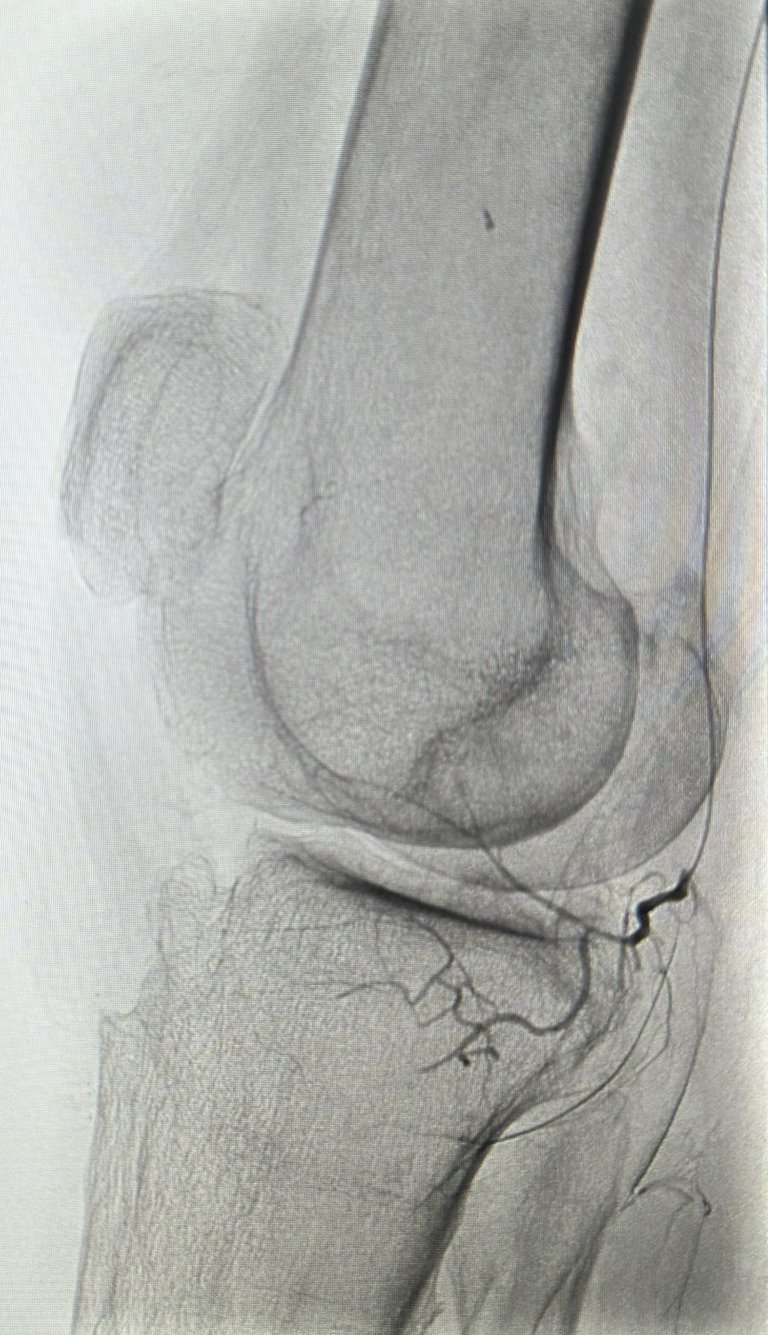

Une artériographie par injection de produit de contraste iodé est réalisée. Elle permet la cartographie des artères à destinée du genou pour repérer les zones d'hypervascularisation et de synovite, qui sont le témoin d'une inflammation locale de la gaine articulaire du genou (la synoviale).

L'objectif de la procédure est de boucher (=emboliser) ces artères anormalement développées qui alimentent les zones inflammatoires de l'articulation, c'est à dire les zones de synovite, pour diminuer l'apport vasculaire et arrêter le cycle de l'inflammation.